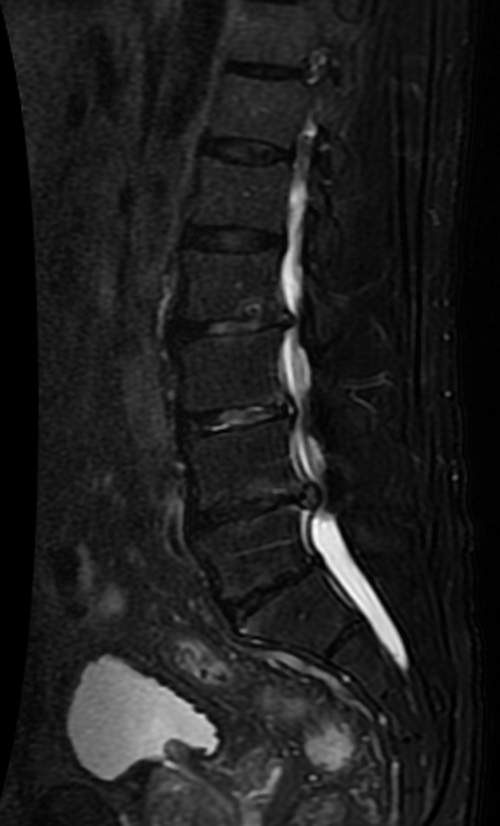

L4-L5 posterolateral disc herniation compressing the L5 nerve root with disc desiccation, annular tear, and...